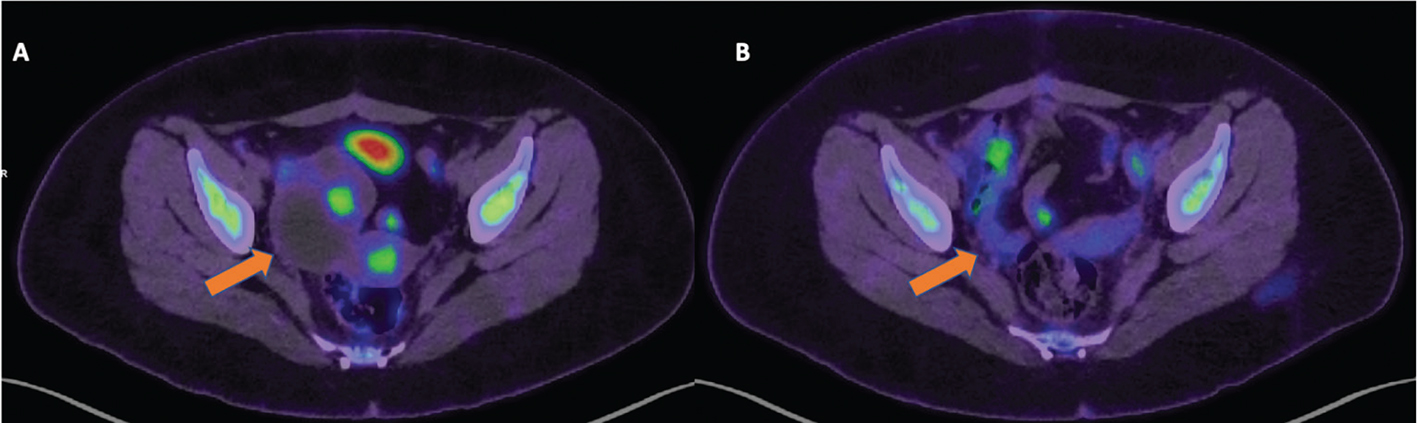

Restaging

The most significant and independent prognostic factor of OS in ovarian cancer patients is the absence or residual disease after primary surgery (28). A positive restaging PET/CT was found to be associated with poor prognosis, and peritoneal spread demonstrated by PET/CT was a significant independent predictor of poor prognosis (33). Moreover, a negative PET/CT has a high negative predictive value (NPV) for the presence of disease and is associated with a very good disease-specific survival rate (Figures 2 and 3).

Fig 2

Figure 2. Restaging. FDG PET/CT images obtained from a 19-yr-old patient with atypical serous ovarian carcinoma referred for restaging following a unilateral oophorectomy and a cystectomy. Image A demonstrates a right-sided malignant ovarian tumor with focal areas of increased FDG accumulation on pre-treatment FDG PET/CT, which demonstrates significant post-treatment improvement in Image B.